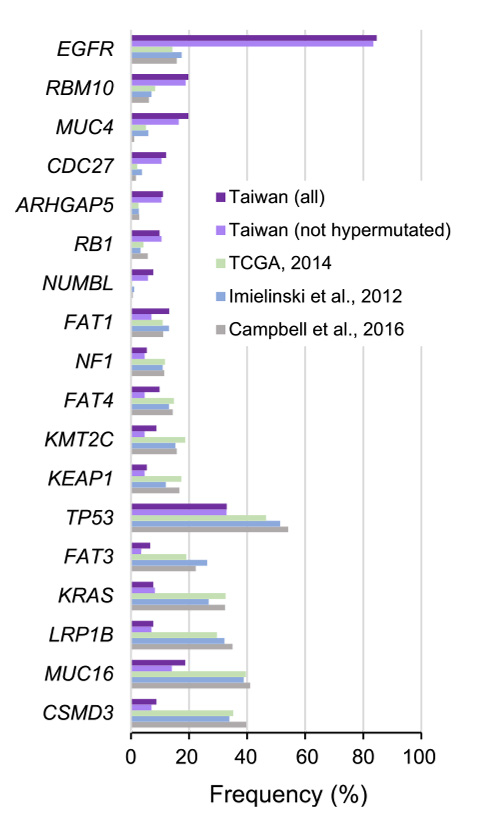

- Ở Đông Á, đặc biệt tại Đài Loan ung thư phổi đã chứng minh được sự nguy hại đáng lưu tâm. Một con số kinh ngạc khi có tới 60% bệnh nhân ung thư phổi ở Đài Loan có đột biến thụ thể yếu tố tăng trưởng biểu bì (Receptor Tyrosine Kinase Epidermal Growth Factor – EGFR), trái ngược hoàn toàn với tỷ lệ dưới 20% ở phương Tây.

Biểu đồ liên quan đến tần suất đột biến được quan sát giữa nghiên cứu về ung thư phổi tại Đài Loan và nghiên cứu ở nước ngoài.

Biểu đồ dạng thanh về tần số đột biến gen cho thấy sự khác biệt đáng kể giữa các nghiên cứu về ung thư phổi ở Đài Loan và ung thư biểu mô tuyến phổi được công bố ở nước ngoài